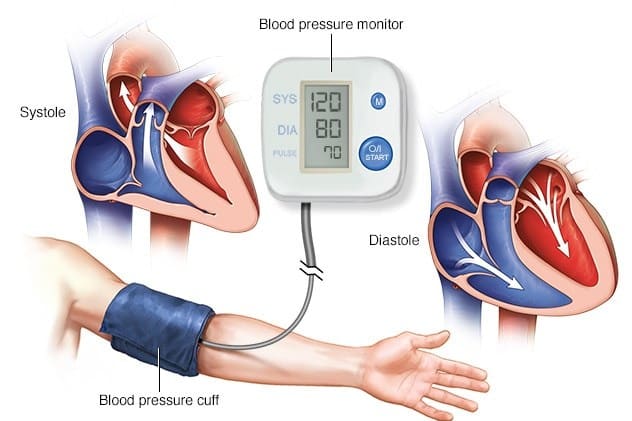

Hypertension Checkup is extremely beneficial for those with high blood pressure, heart disease, or cardiovascular risk factors. This checkup help in preventing any heart related ailments. Dr. Debabrata Sarkar<span...